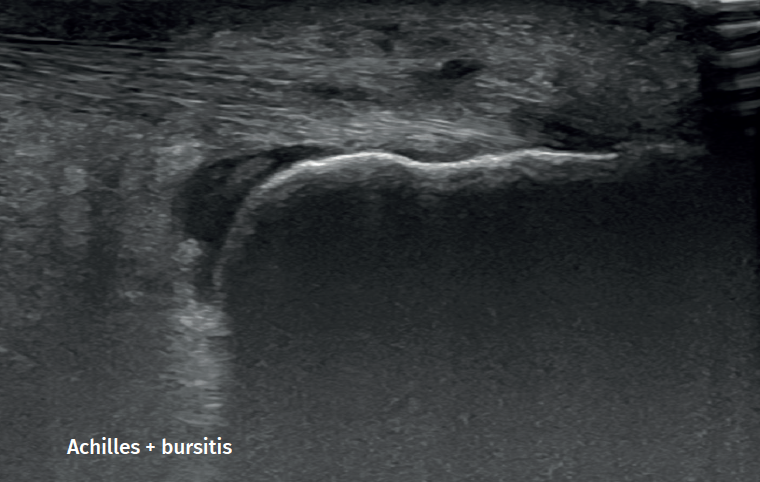

Figure 2. Retroachilleal bursitis.

However, in the chronic forms of insertional Achilles tendinopathy or enthesopathy (present in the distal 2 cm of the tendon), we can observe calcifications within the tendon in the form of traction enthesophytes or at the insertion site in the form of spurs. These conditions are often associated to alterations of the retroachilleal bursa(5,31)(Figure 2).

Retrocalcaneal bursitis is characterized by an increased volume of the bursa, with the possible association of Haglund deformity(25). In the case of retroachilles or superficial calcaneal bursitis we can identify fluid between the skin and the Achilles tendon(5).